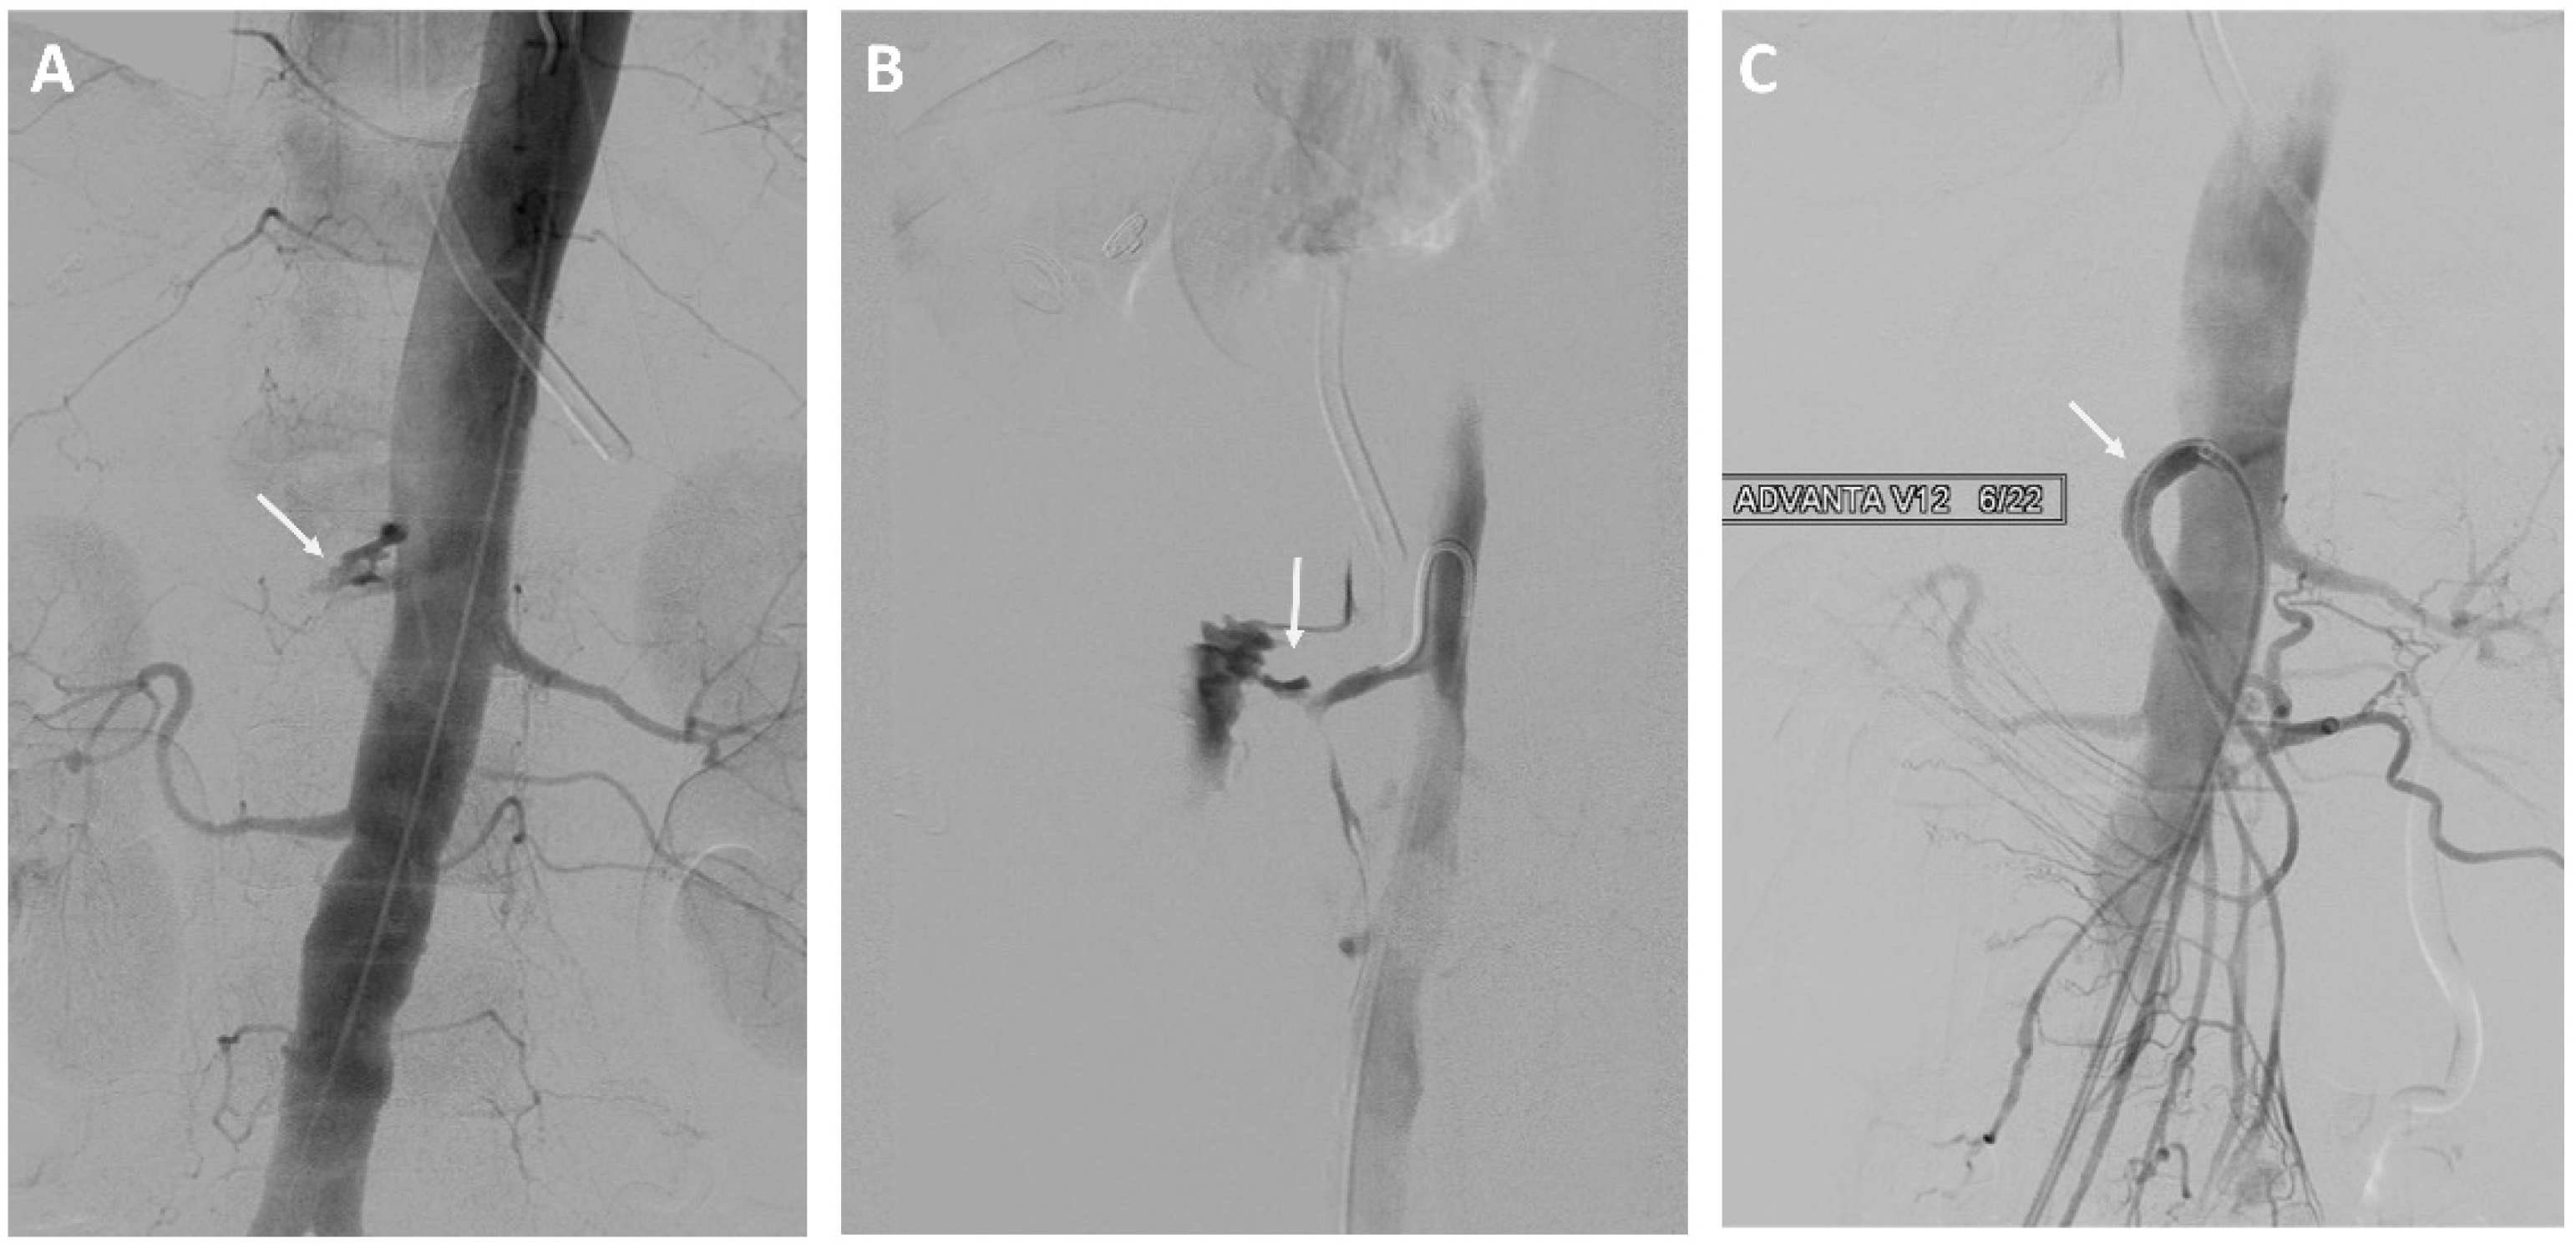

Eight of 37 (22%) patients in the EVT group underwent stent-graft treatment of the eroded vessels: celiac artery (n = 1), common hepatic artery (n = 4) see Figure 1, right hepatic artery (n = 1), and superior mesenteric artery (n = 2) see Figure 2. The stent-grafts used were Advanta V12TM (Getinge, Gothenburg, Sweden) in five patients, PK Papyrus covered stent (BIOTRONIK, Bulach, Switzerland) in one, covered balloon-expandable Jomed stent (Abbott Vascular, Santa Clara, CA, USA) in one, and polytetrafluoroethylene (PTFE)-covered Jostent GraftMaster® (Abbott Vascular, Santa Clara, CA, USA) in one. Technical success was achieved in all cases.

Figure 2.

A 73-year-old woman with a history of intraductal papillary mucinous cancer of the pancreatic head and pylorus preserving pancreatoduodectomy (PPPD). (A,B) Angiography showing bleeding from the superior mesenteric artery. (C) Treatment of the superior mesenteric artery with a stent-graft.